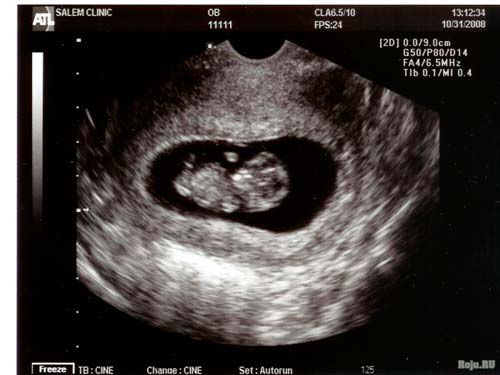

Planuojamas ultragarsas retai atliekamas po 10 savaičių. Bet jei dėl tam tikrų priežasčių planuojamas tyrimas, tai yra proga pažvelgti į savo „vedlį“. Atsižvelgiant į įrangą ir mažyčio kūno padėtį, tamsiame fone galite pamatyti pailgą baltą dėmę ar net savo mažojo vyro kontūrus.

10 savaičių uzi nuotrauka

Šią savaitę labai gerai atsimenu, nes dariau pirmąjį ultragarsą ir, nors praėjo daug laiko, prisimenu, kad vaisiaus dydis buvo 31 mm. Iš visų nėštumo požymių buvo labai stiprus pykinimas ir vėmimas bei odos patamsėjimas šalia spenelių.